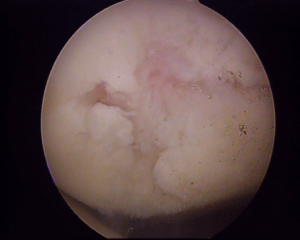

• Την Αρθροσκόπηση της πάσχουσας άρθρωσης για έλεγχο τυχών ενδοαρθρικών κακώσεων και την αντιμετώπιση τους.

Η χειρουργική θεραπεία εξαρτάται από το μέρος του σώματος και συνήθως γίνεται με χειρουργική ελάχιστης επεμβατικότητας ή αρθροσκοπικές τεχνικές. Η θεραπεία περιλαμβάνει συρραφή των κολοβωμάτων του τένοντα ή επανακαθήλωση του στο οστό με ειδικά υλικά απόλυτα βιοσυμβατά.